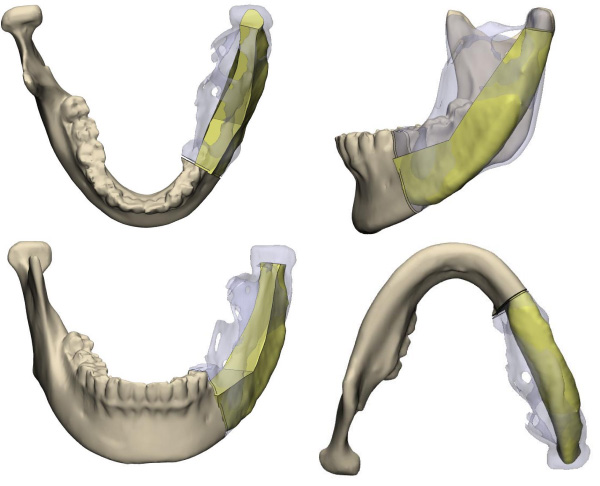

頜骨外形不規則,將髂骨塑形為下頜骨的形狀非常困難,稍有誤差,不但影響患者外形,還會出現咬合紊亂的情況……這是一臺只許成功不許失敗的手術,所有環節都容不得一點馬虎,為了能夠精細塑形,口腔科專家采用了先進的3D模擬技術制作出各個截骨引導板,在術前進行多次模擬重建手術,確保萬無一失。

手術當天,口腔科手術團隊首先按照術前設計并3D模擬的截骨導板對下頜骨及腫瘤精準切除;再根據術前設計的髂骨截骨導板精準取骨和精準切割塑形拼接,后把移植骨的動脈和靜脈在顯微鏡下吻合到頸部的動脈和靜脈血管上,重建血循環,恢復功能,經過十多個小時的努力,終于圓滿完成了下頜骨缺損重建。